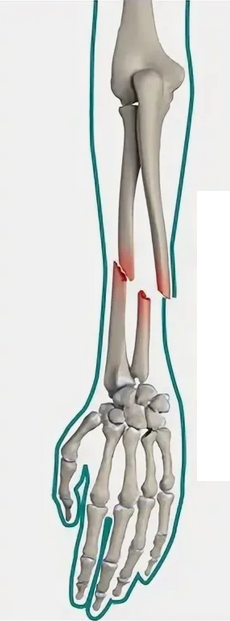

В случае перелома шейки бедра компания МосРентген Центр госпитализирует в Склиф для эндопротезирования.